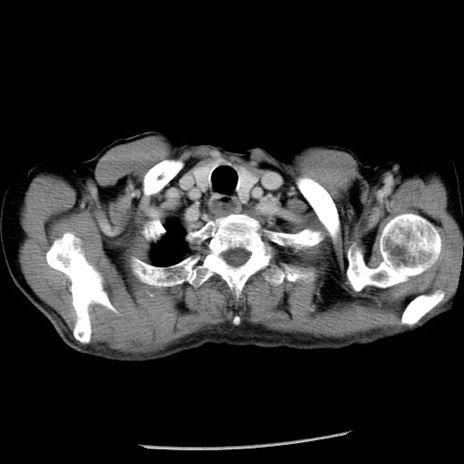

症例26(横断像)

【症例】80歳代男性

【主訴】嘔吐

【現病歴】昨晩2回嘔吐あり、今朝になっても嘔吐あり。来院。

【既往歴】胃潰瘍

【身体所見】意識清明、BT 37.6℃、BP 166/95mmHg、HR 100bpm、SpO2 97%、腹部:平坦・軟、腸蠕動音聴取良好、圧痛なし。

【データ】WBC 21900、CRP 1.46